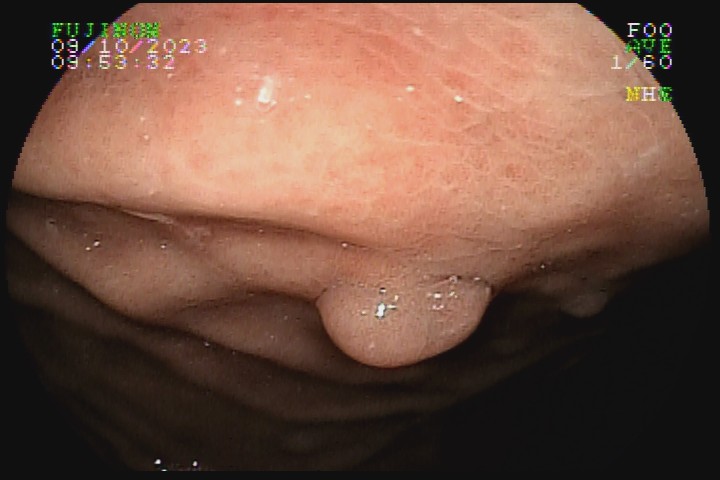

São decorrentes da hiperplasia focal de glândulas da mucosa fúndica, geralmente múltiplos, menores que 5mm, acometendo o fundo e corpo gástricos. A incidência aumentada na atualidade está relacionada com a utilização dos IBP, que parece favorecer a hiperplasia das glândulas. Endoscopicamente, apresentam a mucosa lisa e regular, com coloração pálida e vascularização evidente. Seu potencial de malignização é mínimo.